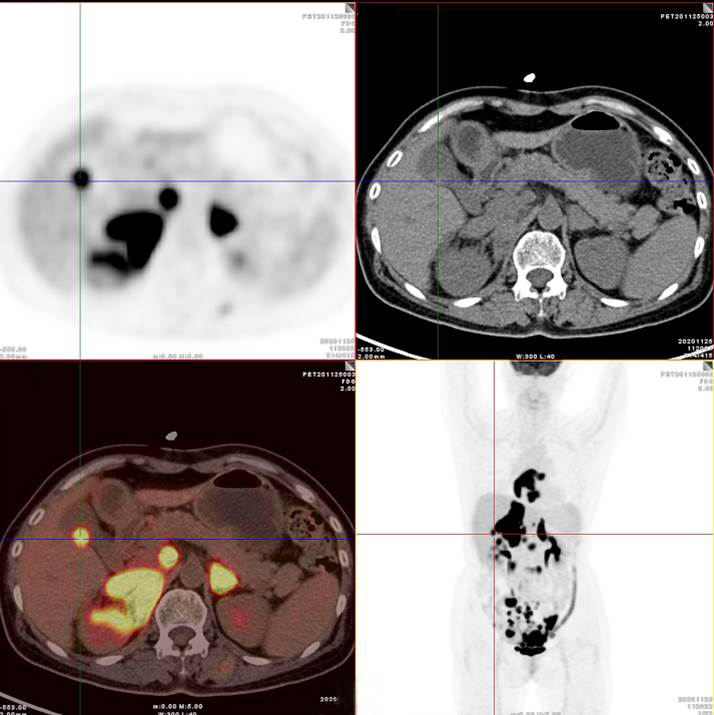

【厦门高尚医学影像病例】PET/CT诊断淋巴瘤的应用价值